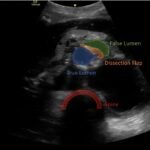

Although uncommon, acute aortic dissections are a life-threatening, cannot miss diagnosis for the emergency medicine clinician. Point of care ultrasound can play an integral role in the initial work up of the undifferentiated patient. While not initially utilized to make the diagnosis of aortic dissection, the ultrasound images obtained in this case describe key findings on ultrasound vital for an emergency clinician to recognize. It is essential for emergency medicine clinicians to differentiate an aortic dissection from other causes of chest pain and abdominal pain because the quick mobilization of resources plays a key role in the management and outcome of such patients.

Aortic dissection, vascular, dissection flap, back pain, point of care ultrasound, POCUS.